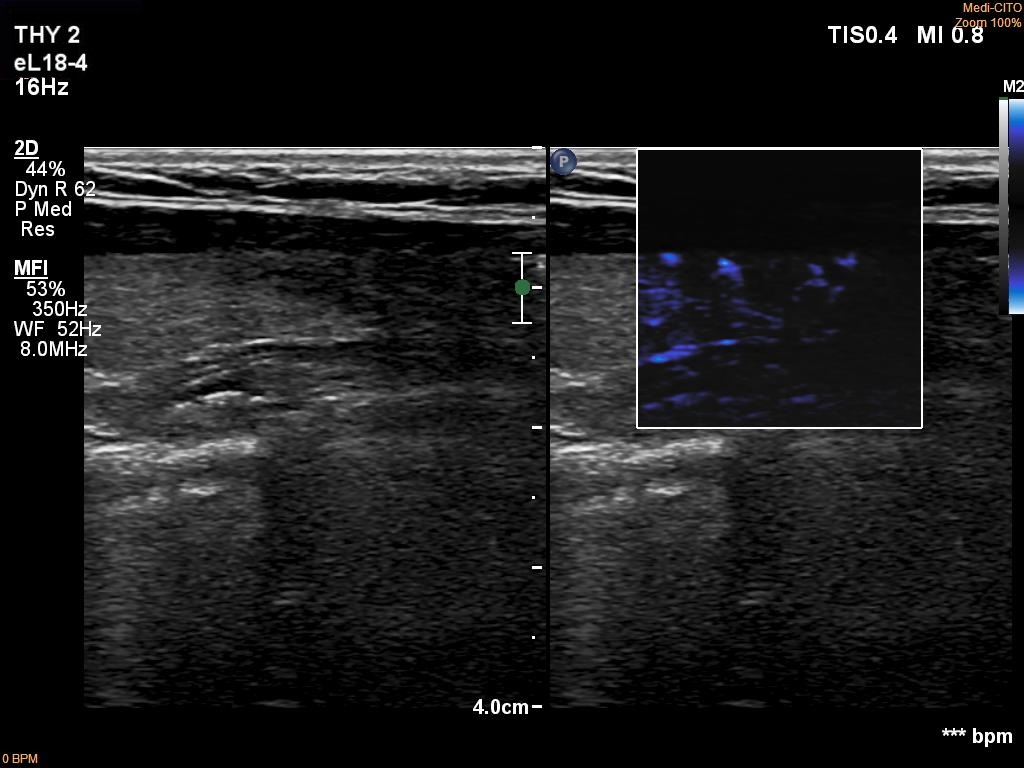

Left lobe, longitudinal scan, microflow imaging. The lesion does not have intralesional vessels.